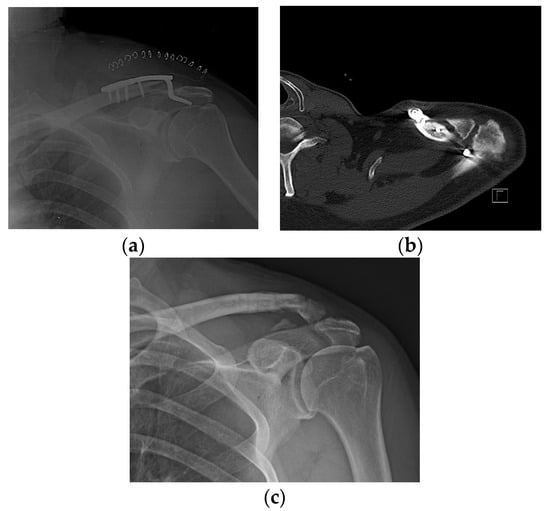

PSE was noted in 17 of 75 (22.4%) patients with DCF and 13 of 84 (15.5%) patients with ACD. There was no difference in the incidence of PSE between patients with DCF and ACD (p = 0.265). Before removing the hook plate, none of the patients with POM or PSS showed iatrogenic rotator cuff lesions on MRI. However, capsular thickening of the axillary pouch with high signal intensity as a typical finding of frozen shoulder was observed in patients with PSS (Figure 1). After removing the plate with or without surgical release for PSS, such as MUA or ACR, there was no recurrence during the follow-up period.

Figure 1. Typical findings on magnetic resonance imaging (MRI) in patients with painful shoulder stiffness. High signal intensity is observed in thickened joint capsule, which is emphasized on axillary capsular pouch.